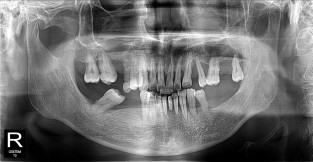

• 2

전체어금니

치료기간 : 2021-11-08 ~ 2022-12-22

1. 상기 x-ray 이미지 모두 동일한 해당 의료기관에서 진료한 환자입니다.

2. 상기 x-ray 이미지 모두 동일 인물의 것입니다.

3. 치료 전 이미지는 2021-11-08에 촬영했으며, 치료 후 이미지는 2022-12-22에 촬영하였습니다.

4. 상기 x-ray 이미지 모두 동일 조건에서 환자분의 동의를 받아촬영되었습니다.

* 임플란트 시술은 환자분의 상태(고혈압, 당뇨 등)에 따라 부작용이 있을 수 있으니, 반드시 전문의와 상담이 필요합니다.

* 임플란트 수술 부작용

: 수술 후 출혈, 교합, 통증, 붓기, 염증 등의 문제점이 발생할 수 있습니다.)